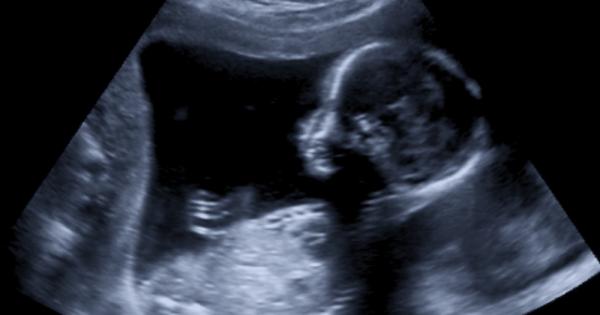

В изключителен медицински подвиг бебе в Обединеното кралство беше ефективно

Американката Джейдън Ашли роди сина си Леви Джеймс на 11

...... в утробата на майката. Според лекарите операцията е била успешна. Бъдещите родители могат да се надяват на пълно възстановяване и нормално развитие на детето, допълни Блиц.